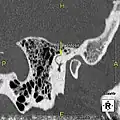

| Exostoses in the ear canal, as seen through otoscopy | |

Exostosis in ear canal

Exostosis in ear canal

Exostosis in ear canal